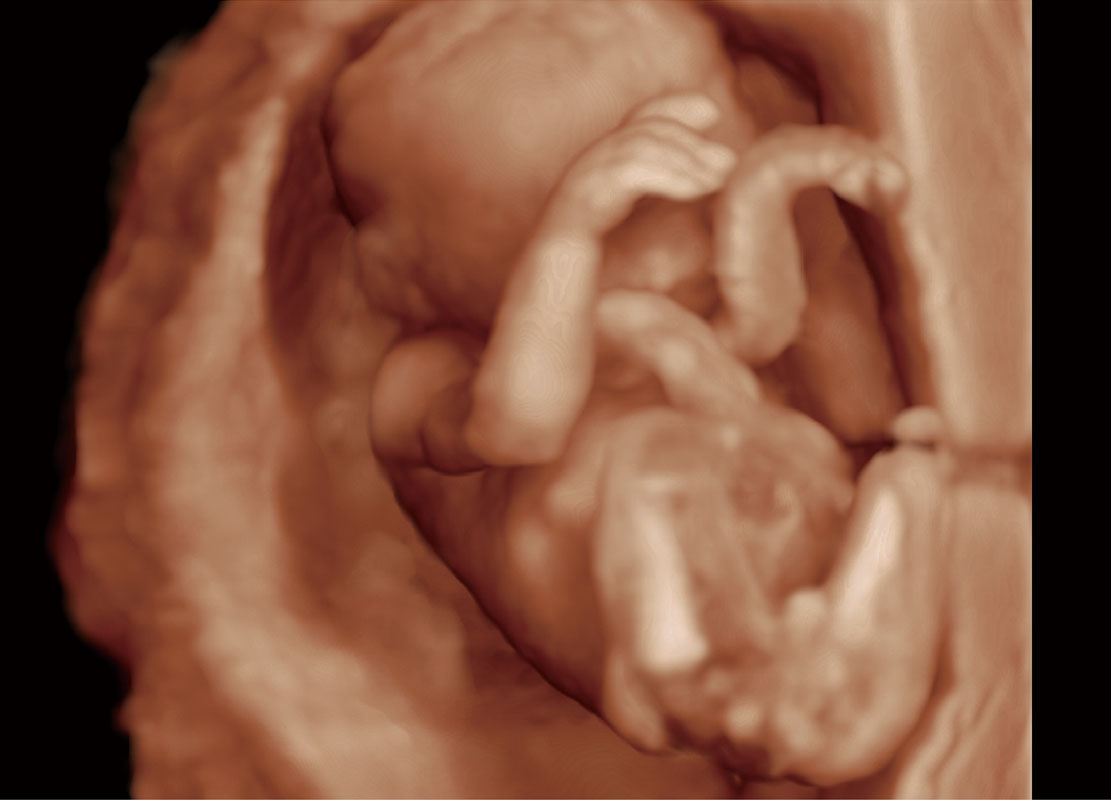

高分辨率容积成像-早孕胎儿

P60在胎儿早孕期超声筛查中为您带来优异的图像质量。